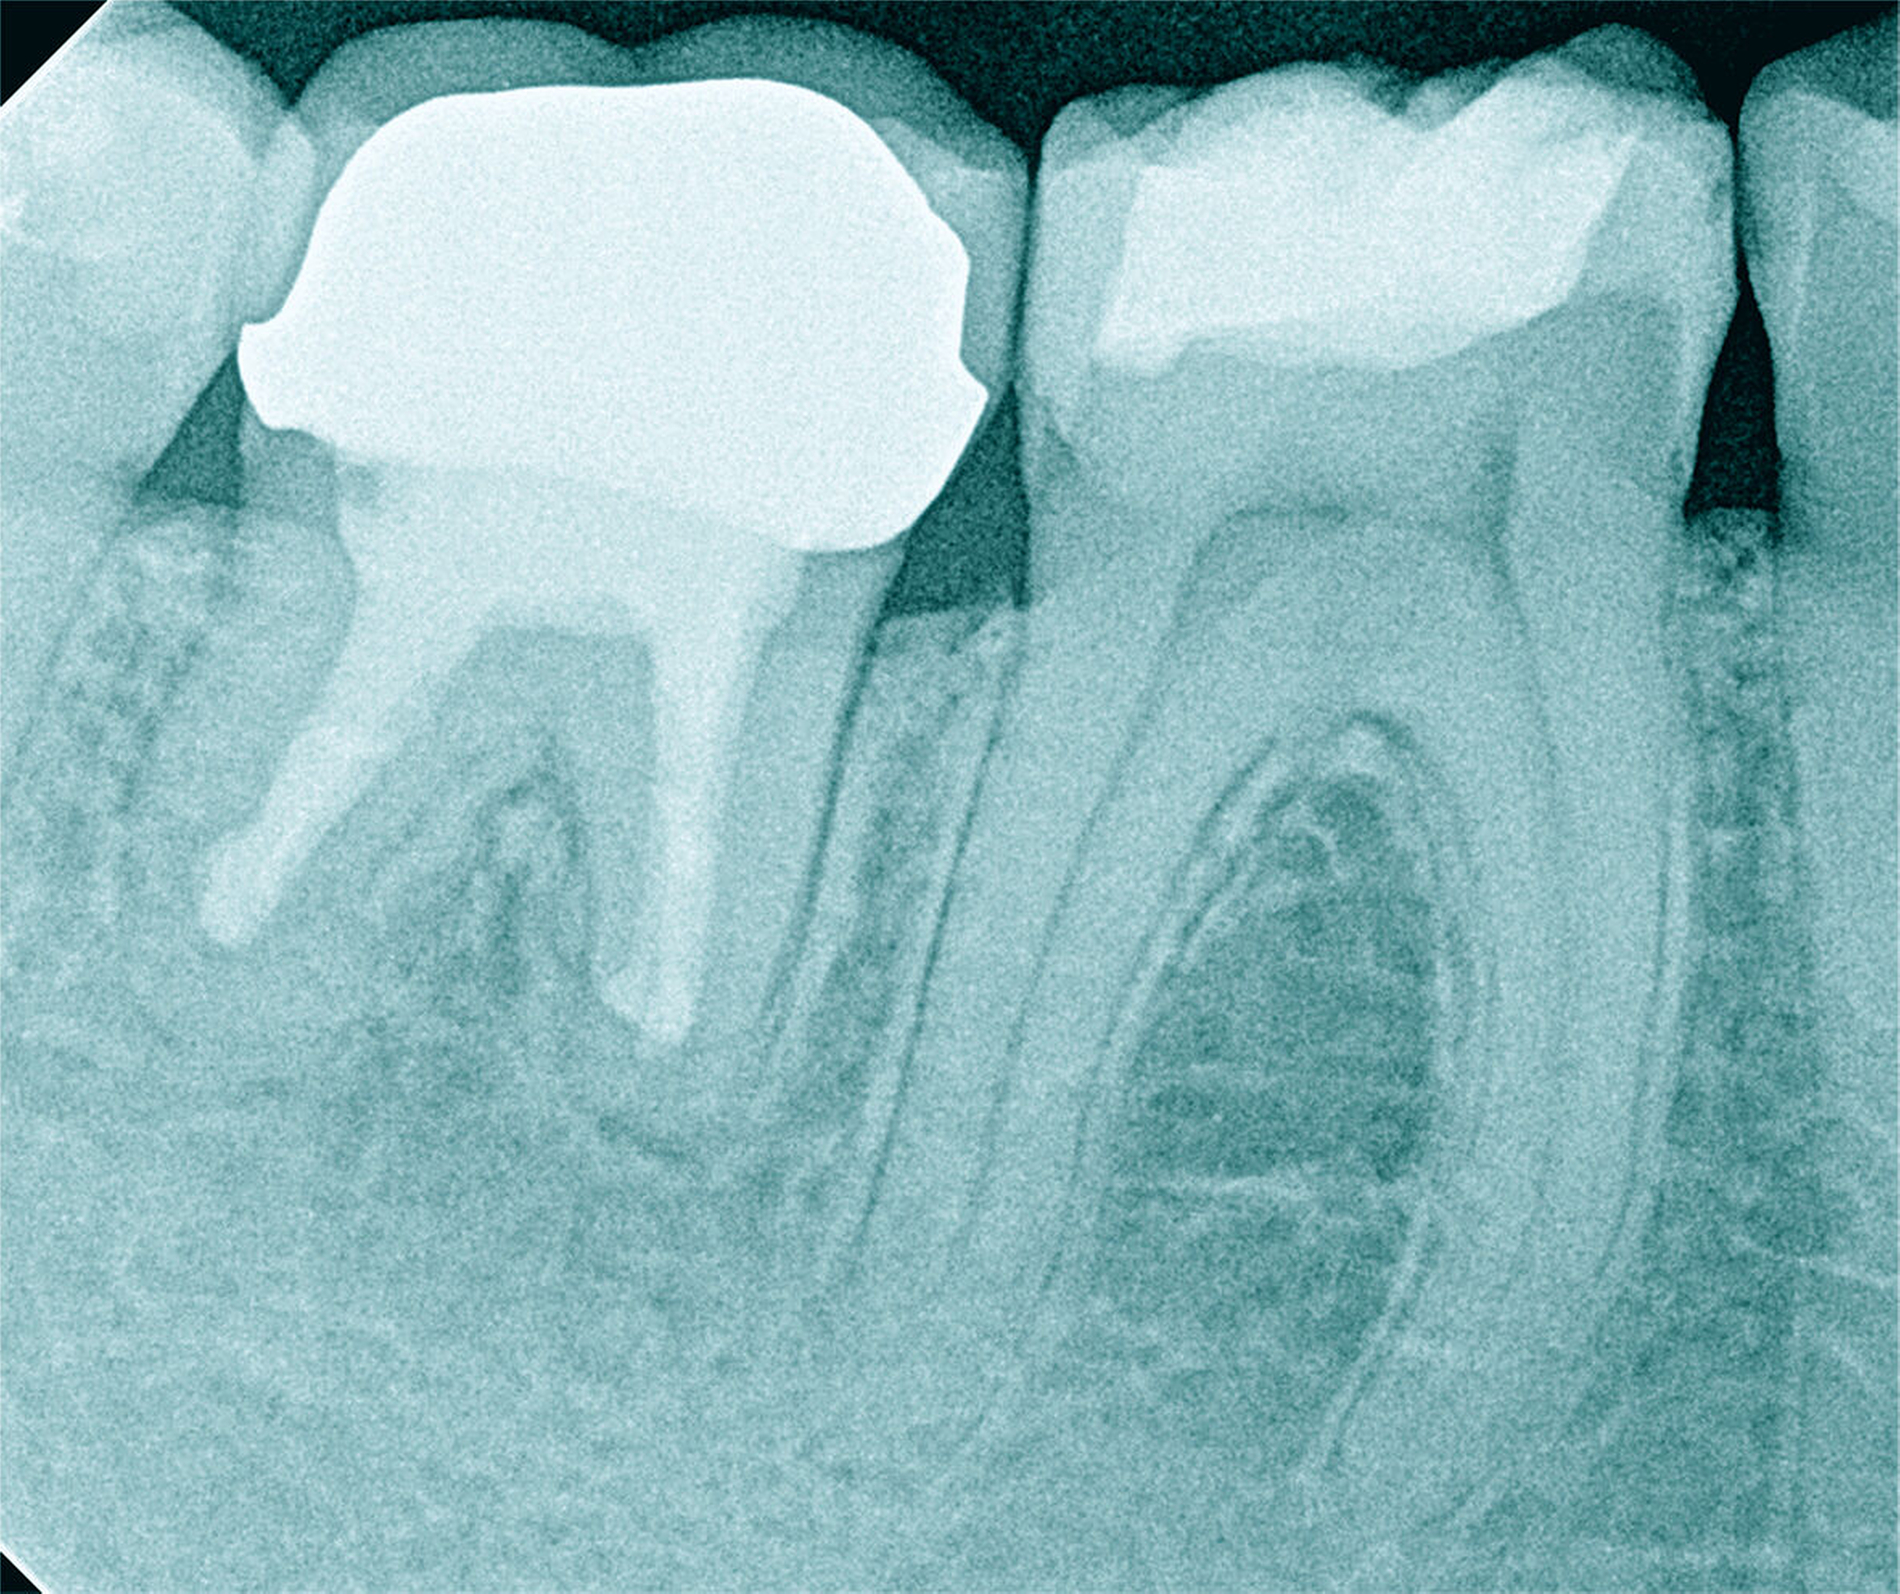

Röntgenbilder können genutzt werden, den anatomischen Schwierigkeitsgrad zu ermitteln. Lässt sich ein Wurzelkanal vollständig bis zum Apex mit einem Krümmungswinkel bis zu 30 Grad und einem großen gleichmäßigen Krümmungsradius erkennen, ist keine erhöhte Schwierigkeit in der Therapie zu erwarten (Abbildungen 1 und 2).

Krümmungsradius: Ist demgegenüber der Verlauf des Wurzelkanals unterbrochen, kann meist mit einer tiefen Wurzelkanalaufteilung gerechnet werden (Abbildung 3) [Reuver, 2002].

Lässt sich der Wurzelkanal auf der Röntgenaufnahme nur apikal erkennen, liegt meist eine Kalzifikation der Pulpa vor, die häufig erst unter Nutzung einer optischen Vergrößerung überwunden werden kann [Kiefner et al., 2017].